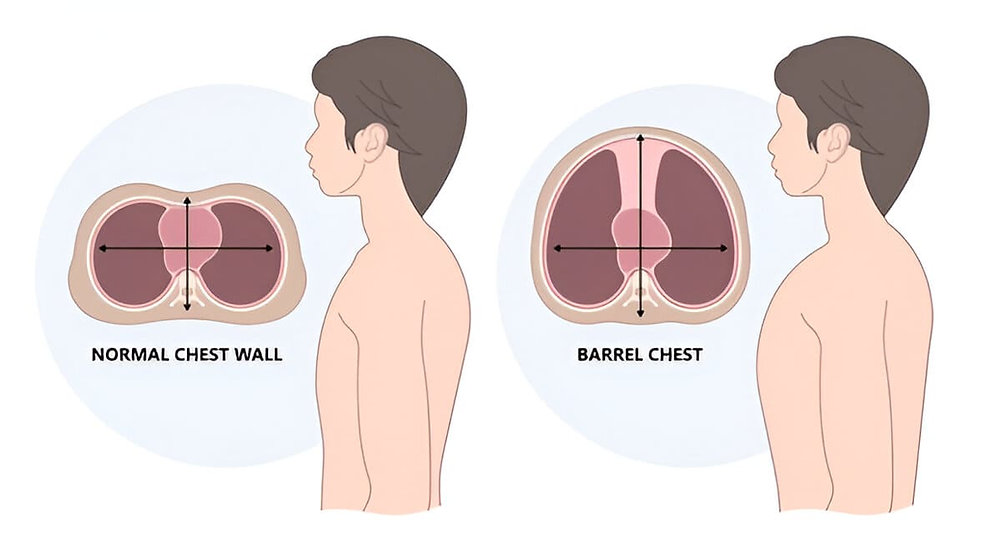

- ચેસ્ટને સિમ્મેટ્રી, શેપ તેમજ ડીફોરમીટી માટે એક્ઝામિન કરવી.

- ચેસ્ટ એ નોર્મલ શેપ ધરાવે છે કે બેરેલ, પીજન અથવા ફનેલ શેપ ધરાવે છે કે નહિ તે ચેક કરવું.

- નોર્મલ હેલ્ધી પર્સનમાં ચેસ્ટનો શેપ ઈલેપટીકલ (લંબગોળ) હોય છે.

- નોર્મલ હેલ્ધી પર્સનમાં એન્ટેરિયર પોસ્ટેરિયર ડાયામીટર 1 હોય છે જ્યારે લેટરલ ડાયામીટર 2 હોય છે.

- નોર્મલ હેલ્ધી પર્સનમાં એન્ટેરિયર પોસ્ટેરિયર અને ટ્રાન્સવર્સ ડાયામીટરનો રેશિયો 1:2 હોય છે.

Barrel chest (બેરલ ચેસ્ટ):

- બેરલ ચેસ્ટ એ લંગના ઓવર ઇન્ફલેશનને કારણે જોવા મળે છે. એલ્વીઓલાયની ઇલાસ્ટિકસીટી ઘટી જવાને કારણે તે ફુલાયેલા જોવા મળે છે.જેના કારણે તે રાઉન્ડ બલ્જિંગ ચેસ્ટ દેખાય છે અને તે Barrel chest (બેરલ ચેસ્ટ) જેવી લાગે છે.

- બેરલ ચેસ્ટમાં એન્ટેરિયર પોસ્ટેરીયર ડાયામીટર વધીને 2 થઈ જાય છે. આથી એન્ટેરિયર પોસ્ટેરીયર ડાયામીટર અને લેટરલ ડાયામીટરનો રેશિયો 1:1 જોવા મળે છે.

- COPD અને એમ્ફાયસેમા વાળા પેશન્ટમાં બેરલ ચેસ્ટ જોવા મળે છે.